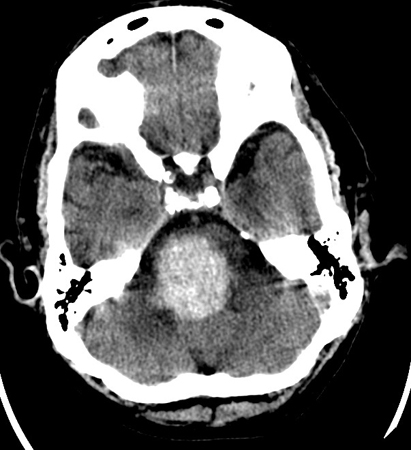

[Figure caption and citation for the preceding image starts]: Hemorragia del tallo cerebral en el mesencéfalo que se extendió a partir de una hemorragia hipertensiva en el puente troncoencefálicoDe la colección personal del Dr. G. Bryan Young; utilizada con autorización [Citation ends].

[Figure caption and citation for the preceding image starts]: Hemorragia hipertensiva en el puente troncoencefálico que ingresó en el cuatro ventrículo y se extendió hacia el mesencéfaloDe la colección personal del Dr. G. Bryan Young; utilizada con autorización [Citation ends].